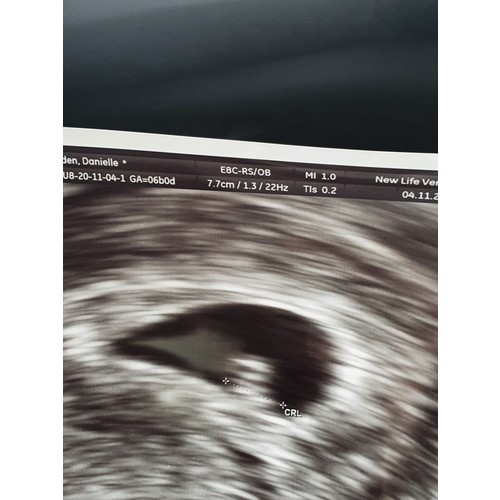

Deze echo was ik 6w3d (ik dacht zelf verder te zijn). Ook bij mij dachten ze dat t niet goed was, omdat het te klein zou zijn. Ben op dit moment inmiddels 17w zwanger. Houd hoop en ik duim met je mee!